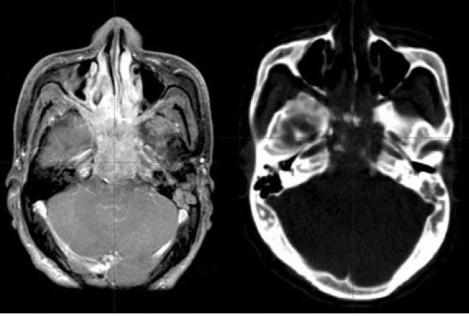

Опухоли носоглотки

Основной гистологический вариант опухолей этой зоны - плоскоклеточный рак. Встречаются недифференцированный рак (30%), лимфосаркома и лимфоэпителиома.

Злокачественные опухоли глотки в структуре онкологических заболеваний составляют около 3%. Около 50% этих опухолей локализуется в носоглотке. Около 85% злокачественных опухолей носоглотки эпителиального происхождения, 7% составляют лимфомы. Рак носоглотки чаще возникает у молодых людей. Мужчины болеют в 3-4 раза чаще женщин.

Симптомы зависят от вариантов инвазии соседних органов. Рак носоглотки может распространяться по стенке глотки вниз с захватом мягкого неба, при этом затрудняется акт глотания, возникает охриплость голоса, кашель. У 30% больных опухоль прорастает в носовую полость, вызывая выделения из носа, гнусавую речь, затруднение дыхания через нос. При возникновении опухоли в боковых отделах нарушается проходимость слуховой (евстахиевой) трубы, понижается слух. При распространении опухоли в полости черепа возникают головные боли, диплопия, потеря зрения и другие симптомы.